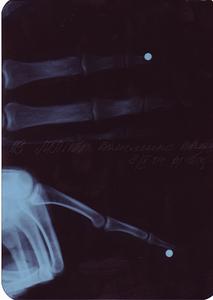

а вот что с руками

с кровью- стреляли из CP-88 Competition

шрам - 3.5 см в глубину от входного отверстия

ренген - стреляли из МР 651